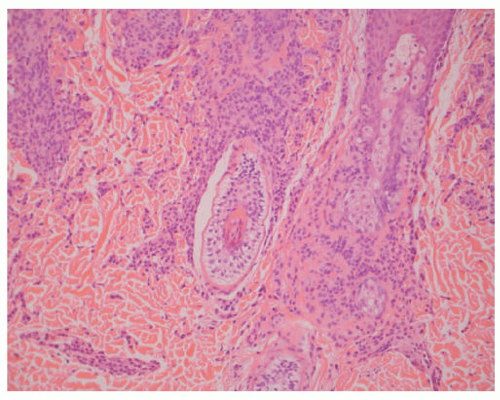

FIGURE 22-7. Compound melanocytic nevus. This lesion from the postauricular region of a 9-year-old female shows the small individual nevus cells compared to the larger more superficial nevus cells. Also note the loss of the nesting pattern around the hair follicle with congenital-like features.

Dermal Nevus

DN is defined as a melanocytic lesion without a junctional component. It is often characterized as a soft dome-shaped lesion whose differential diagnosis may include neurofibroma. Both the compound nevus and DN may be associated with alterations in the overlying epidermis including marked acanthosis or seborrheic keratosis-like architecture. With the loss of the junctional component, DN often appears lighter in color. Although we generally do not divide DN into the so-called Unna and Miescher patterns, the former is recognized by a widened papillary dermis, whereas the latter has a more diffuse infiltrative growth into the reticular dermis (Figure 22-8A-C).30 Those DNs with the diffuse pattern can have a prominent fibrillary matrix or stroma and tactile body-like formations that have been referred to as neurotization with a resemblance to a neurofibroma. Adipose tissue and heterotopic bone (osteonevus of nanta) are other less common findings whose presence reflects the range of mesenchymal differentiation in NC-derived proliferations. Though uncommon in DNs from children, so-called ancient changes can be mistaken for melanoma.31 Exclusively dermal-based melanocytic nevi are seen in several other specific contexts including the SN, DPN, BN, and CMN.